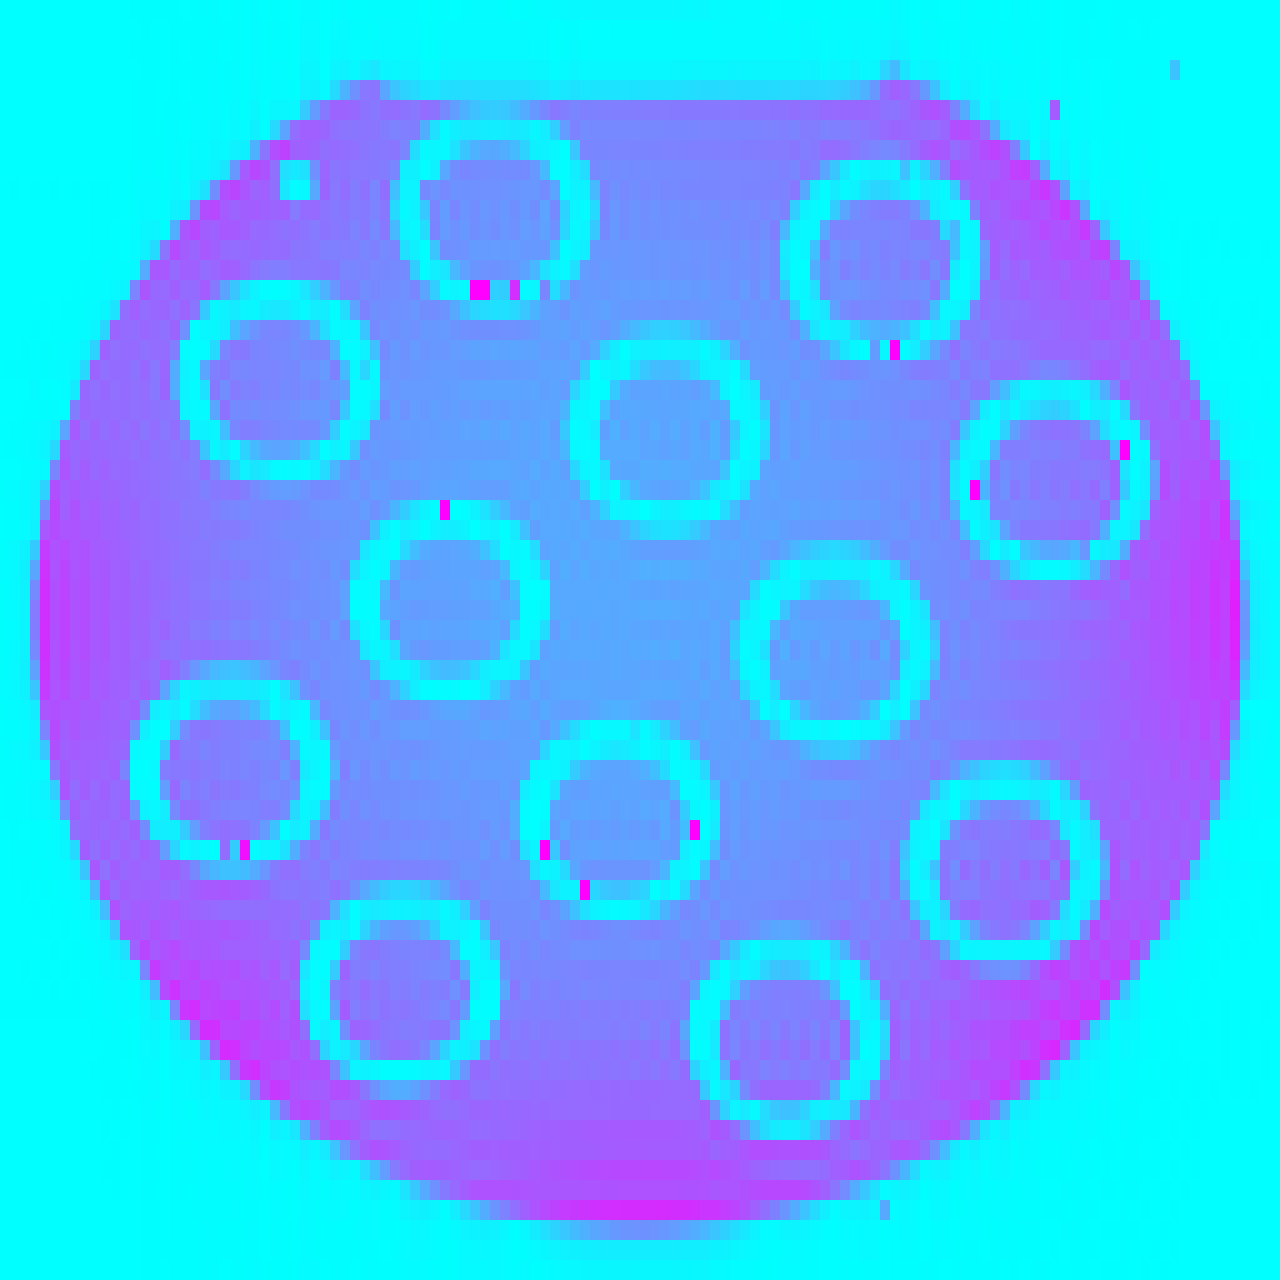

Figure 1 shows a 8×8888\times 8 patch of k-space generated by the patterns with acceleration factor 𝑹=[2,3]𝑹23\bm{R}=[2,3] and Q=72𝑄72Q=72. In this visualisation, each pie slice corresponds to one readout and has a constant area. Hence, the area of each pie corresponds to the number of times with which that k-space position is sampled in the entire acquisition.

Refer to caption

(a) Regular

(b) Treg

(c) Sreg

(d) TSreg

(e) Random

(f) Halton

(g) Legend

Fig. 1: Graphical representation of undersampling patterns for 𝑹=[2,3]𝑹23\bm{R}=[2,3], k-space size of 8×8888\times 8 and number of contrasts Q=72𝑄72Q=72. Legend: each row represents a set of contrasts, grouped together with according to contrast property such as inversion times.